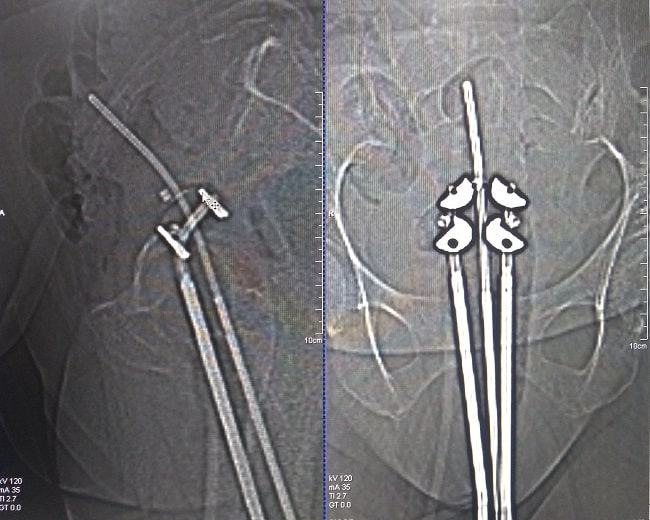

Brakhiterapi adalah bentuk khusus dari radioterapi yang terdiri dari penempatan tepat sumber radioaktif langsung ke dalam atau pada jarak sangat dekat dengan tumor. Meskipun pada awalnya hanya digunakan untuk pengobatan kanker, brakhiterapi juga telah dilaporkan bermanfaat dalam penatalaksanaan penyakit non-malignansi. Contohnya adalah dalam pencegahan restenosis vaskular dan pengobatan keloid.[1,2]

Brakhiterapi dapat digunakan pada berbagai kondisi medis. Brakhiterapi telah dilaporkan bermanfaat dalam pengelolaan kanker payudara, kanker prostat, kanker paru, kanker esofagus, dan berbagai jenis keganasan lain.[2]

Pemberian radiasi untuk tujuan terapi dapat dilakukan lewat beberapa teknik, yakni radiasi eksterna, brakhiterapi, dan lewat pemberian radiofarmaka dengan dosis ablatif. Karena pada brakhiterapi sumber radioaktif diletakkan di dalam atau pada jarak yang sangat dekat dengan kanker, dosis radiasi yang diterima pada kanker sangat tinggi bila dibandingkan dengan jaringan normal sekitarnya.[3] Hal tersebut memberikan keunggulan dosimetri bagi teknik brakhiterapi bila dibandingkan dengan radiasi eksterna.[4]